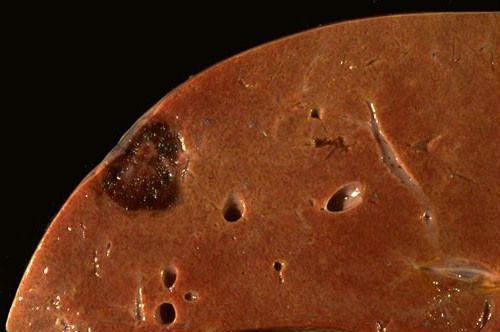

На разрезе выглядит как губка, наполненная кровью и пронизанная ходами и отверстиями.

Окончательный диагноз ставит гистолог, исследуя микропрепарат ткани. Под микроскопом видны большие полости в дерме и гиподерме.

На печени гемангиома может быть только одна, известны случаи, когда формируются множественные новообразования. Размеры гемангиомы печени колеблются в промежутке от 2 мм до 20 см. В ходе визуального осмотра видно, что поверхность опухоли плоская или бугристая (из-за множественных повреждений).

Основным симптомом гемангиомы становится ее цвет, он красновато-синий, хорошо отличимый от окружающих тканей. Большие по размеру опухоли обычно имеют ножку. Замечено, что правая доля печени более подвержена формированию гемангиом, чем левая.

Кавернозная гемангиома печени – это:

- несколько крупных полостей, имеющих внутренние стенки;

- сформированные из фиброзной ткани.

Кавернозная гемангиома печени — это опухоль, структура которой представлена множеством сосудистых полостей. Другое название образования — пещеристое, поскольку полости напоминают пещеры, внутри которых содержится кровь. Снаружи сосуды покрыты оболочкой из соединительной ткани.

Узел может возникать в одной или двух долях печени. Диаметр новообразования колеблется от 2 до 20 см. Патанатомия опухолевого процесса — сосудистый узел, или несколько узлов в разных частях печени. На микропрепарате строение гемангиомы представлено множеством разросшихся сосудов, образующих полости.